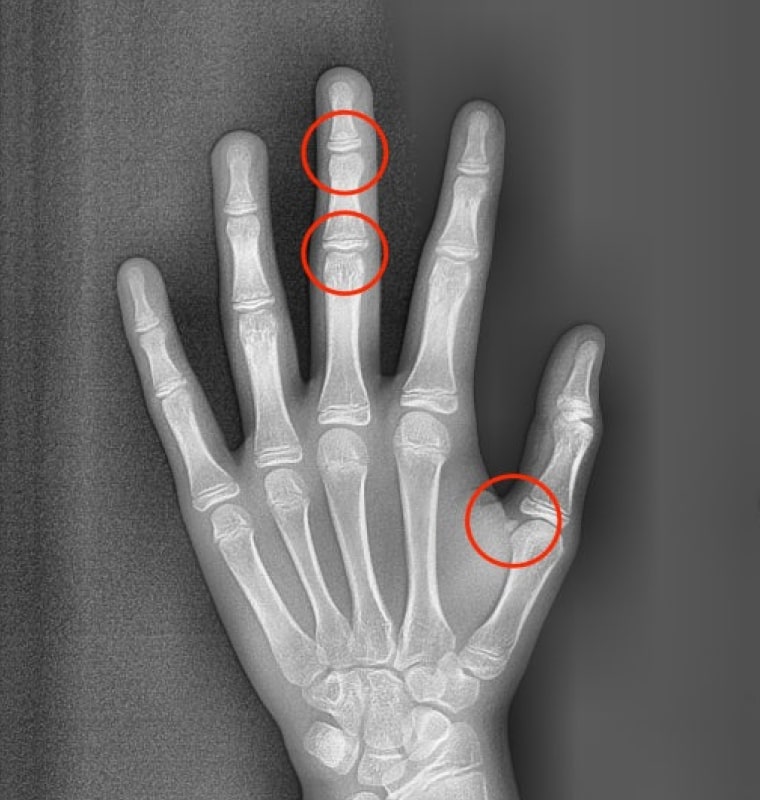

STEP 02 종자골 출현 + 가운데 손가락 마디뼈 미융합

사춘기 급성장기의 초기 또는 중간 단계를 나타내며

이 시기에 교정 치료를 시작하면 골격 문제와 부정교합을

효과적으로 해결할 수 있습니다.

적절한 시기에 치료를 시작함으로써 성장기 동안

최상의 결과를 얻을 수 있습니다.